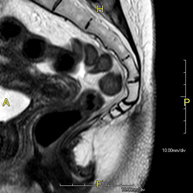

- RM Pelvis masculina

Prueba diagnóstica no invasiva que consiste en la obtención de imágenes de alta definición anatómica de la pelvis masculina mediante el empleo de un campo electromagnético y ondas de radio (con un emisor y un receptor). No utiliza radiación ionizante. No requiere de preparación previa. En algunas ocasiones requiere el empleo de contraste paramagnético (Gadolinio) para caracterizar las lesiones. Esta prueba permite valorar órganos como la vejiga urinaria, la unión entre los uréteres y la vejiga, la próstata, las vesículas seminales, la uretra, los huesos de la pelvis, etc.